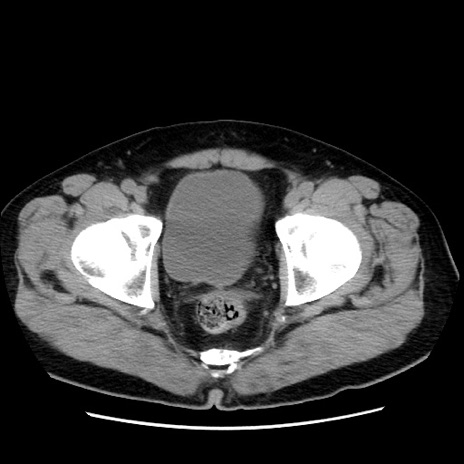

症例16(横断像)

【症例】 70歳代男性

【主訴】 腹痛、嘔吐

【現病歴】 約1ヶ月前より間欠的に腹痛と嘔吐あり、当院消化器内科を受診したところCTで多発する肝臓のLDAを指摘され、精査中であった。以降は消化器症状は安定していたが、2日前より嘔気と腹痛があり、同日より排便・排ガスが消失した。改善認めず、 本日、救急外来を受診した。

【既往歴】 大腸ポリープ切除後。

【身体所見】意識清明・会話良好、BT 36.3℃、BP 127/80mmHg、 P 80bpm、腹部:膨満あり、平坦・軟、上腹部正中および下腹部正中に圧痛あり、反跳痛なし、筋性防御なし。

【データ】WBC 7200、CRP 0.77